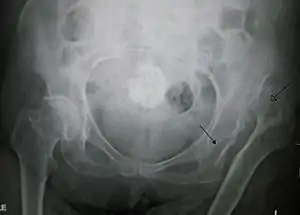

![]() Вроджений вивих лівого стегна у старшої людини. Стрілкою з темним кінцем позначено кульшову впадину, стрілкою зі світлим кінцем — голівку стегна. Вроджений вивих лівого стегна у старшої людини. Стрілкою з темним кінцем позначено кульшову впадину, стрілкою зі світлим кінцем — голівку стегна. | |

Дисплазія кульшового суглоба, діагностована за допомогою УЗД[41] та проекційної рентгенографії («рентген»)[42]. Зазвичай ультразвукова візуалізація є бажаною до 4 місяців через обмежене окостеніння скелета[40][notes 1].

Незважаючи на широке поширення ультразвуку, рентген малого тазу все ще часто використовується для діагностики або моніторингу дисплазії кульшового суглоба або для оцінки інших вроджених станів або пухлин кісток[43]. Найбільш корисні лінії та кути, які можна провести в дитячому тазі для оцінки дисплазії кульшового суглоба, такі: (У дорослих застосовують інші виміри!)